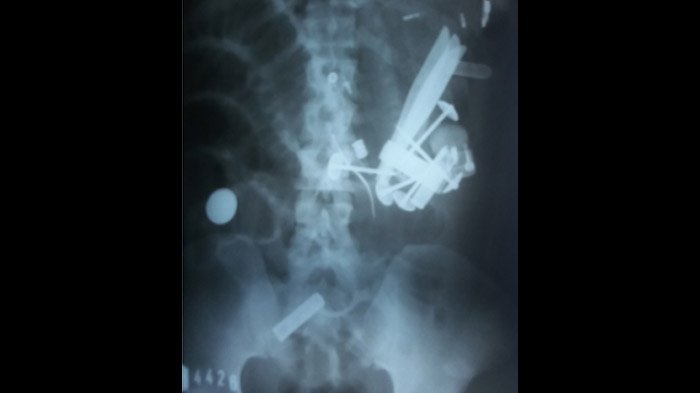

Keluhkan Nyeri di Perut, Hasil Rongent Pria Ini Bikin Merinding, Dari Mana Paku Payung Itu Berasal?

Jarum infus tertancap di tangannya. Dalam kondisi seperti itu, Hendro tak tampak mengeluhkan perutnya yang sering nyeri akibat bersarangnya paku payung dan logam lain dalam usus.

"Empat hari dia tidak mau makan, perutnya kembung, katanya," terang Siti, menceritakan awal mula keluhan nyeri perut Hendro sebelum dibawa ke rumah sakit.

Setidaknya, empat hari Hendro merasakan rasa nyeri yang luar biasa di bagian perut.

Sang ibu dan anggota keluarga lain pun tak pernah mengira bahwa nyeri tersebut akibat bersarangnya logam-logam dalam usus.

Itu sebabnya, Siti kaget bukan kepalang ketika dokter menjelaskan hasil diagnosa rontgen di RSUD Abdoer Rahem, Situbondo, sebelum dirujuk ke RSD dr Soebandi.